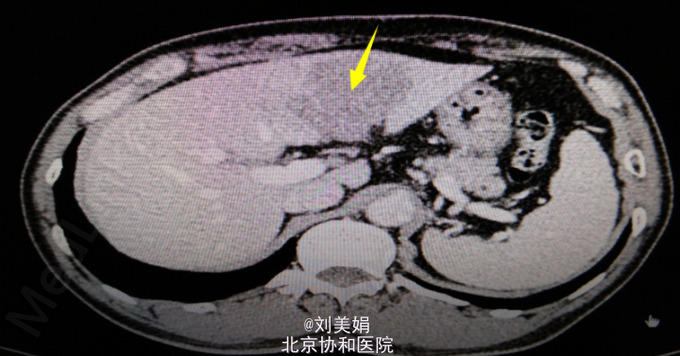

患者 男 58岁 主 诉:乙肝20余年,发现肝脏占位1月余 现病史:患者乙肝病史20余年,间断口服保肝药物,并定期复查肝功,肝功能目前可。每年常规行腹部B超检查,均未见明显异常。1月前体检,行腹部CT发现肝脏占位。患者无畏寒发热、腹痛腹胀、恶心呕吐、皮肤黄染等。于2015年7月10日我院门诊就诊,行腹部增强CT+三维重建示:肝左叶见不规则状稍低密度影,最大截面约为6.0cm×4.6cm,增强后动脉期可见明显强化,门脉期及延迟期强化程度减低,呈“快进快出”强化,肝左动脉分支参与病变供血,门静脉左支局部明显变细,肝门区、小网膜囊内、腹膜后多发淋巴结,部分增大。考虑:肝左内叶占位,考虑恶性病变可能性大;肝左动脉分支参与病变供血,门静脉左支局部明显变细,局部受累可能;肝门区、小网膜囊内、腹膜后多发淋巴结,部分增大。肝肾功:AST 67U/L,LD 254U/L,TBil 13.2μmol/L,DBil 4.5μmol/L,Cr(E) 79μmol/L,ALT 45U/L,Alb 48g/L,GGT 47U/L。

腹部增强CT+三维重建:肝左内叶占位,考虑恶性病变可能性大;肝左动脉分支参与病变供血,门静脉左支局部明显变细,局部受累可能;肝门区、小网膜囊内、腹膜后多发淋巴结,部分增大;双肾多发结石;左肾小囊肿;腹主动脉及其分支动脉粥样硬化性改变;胸腰椎骨质增生。